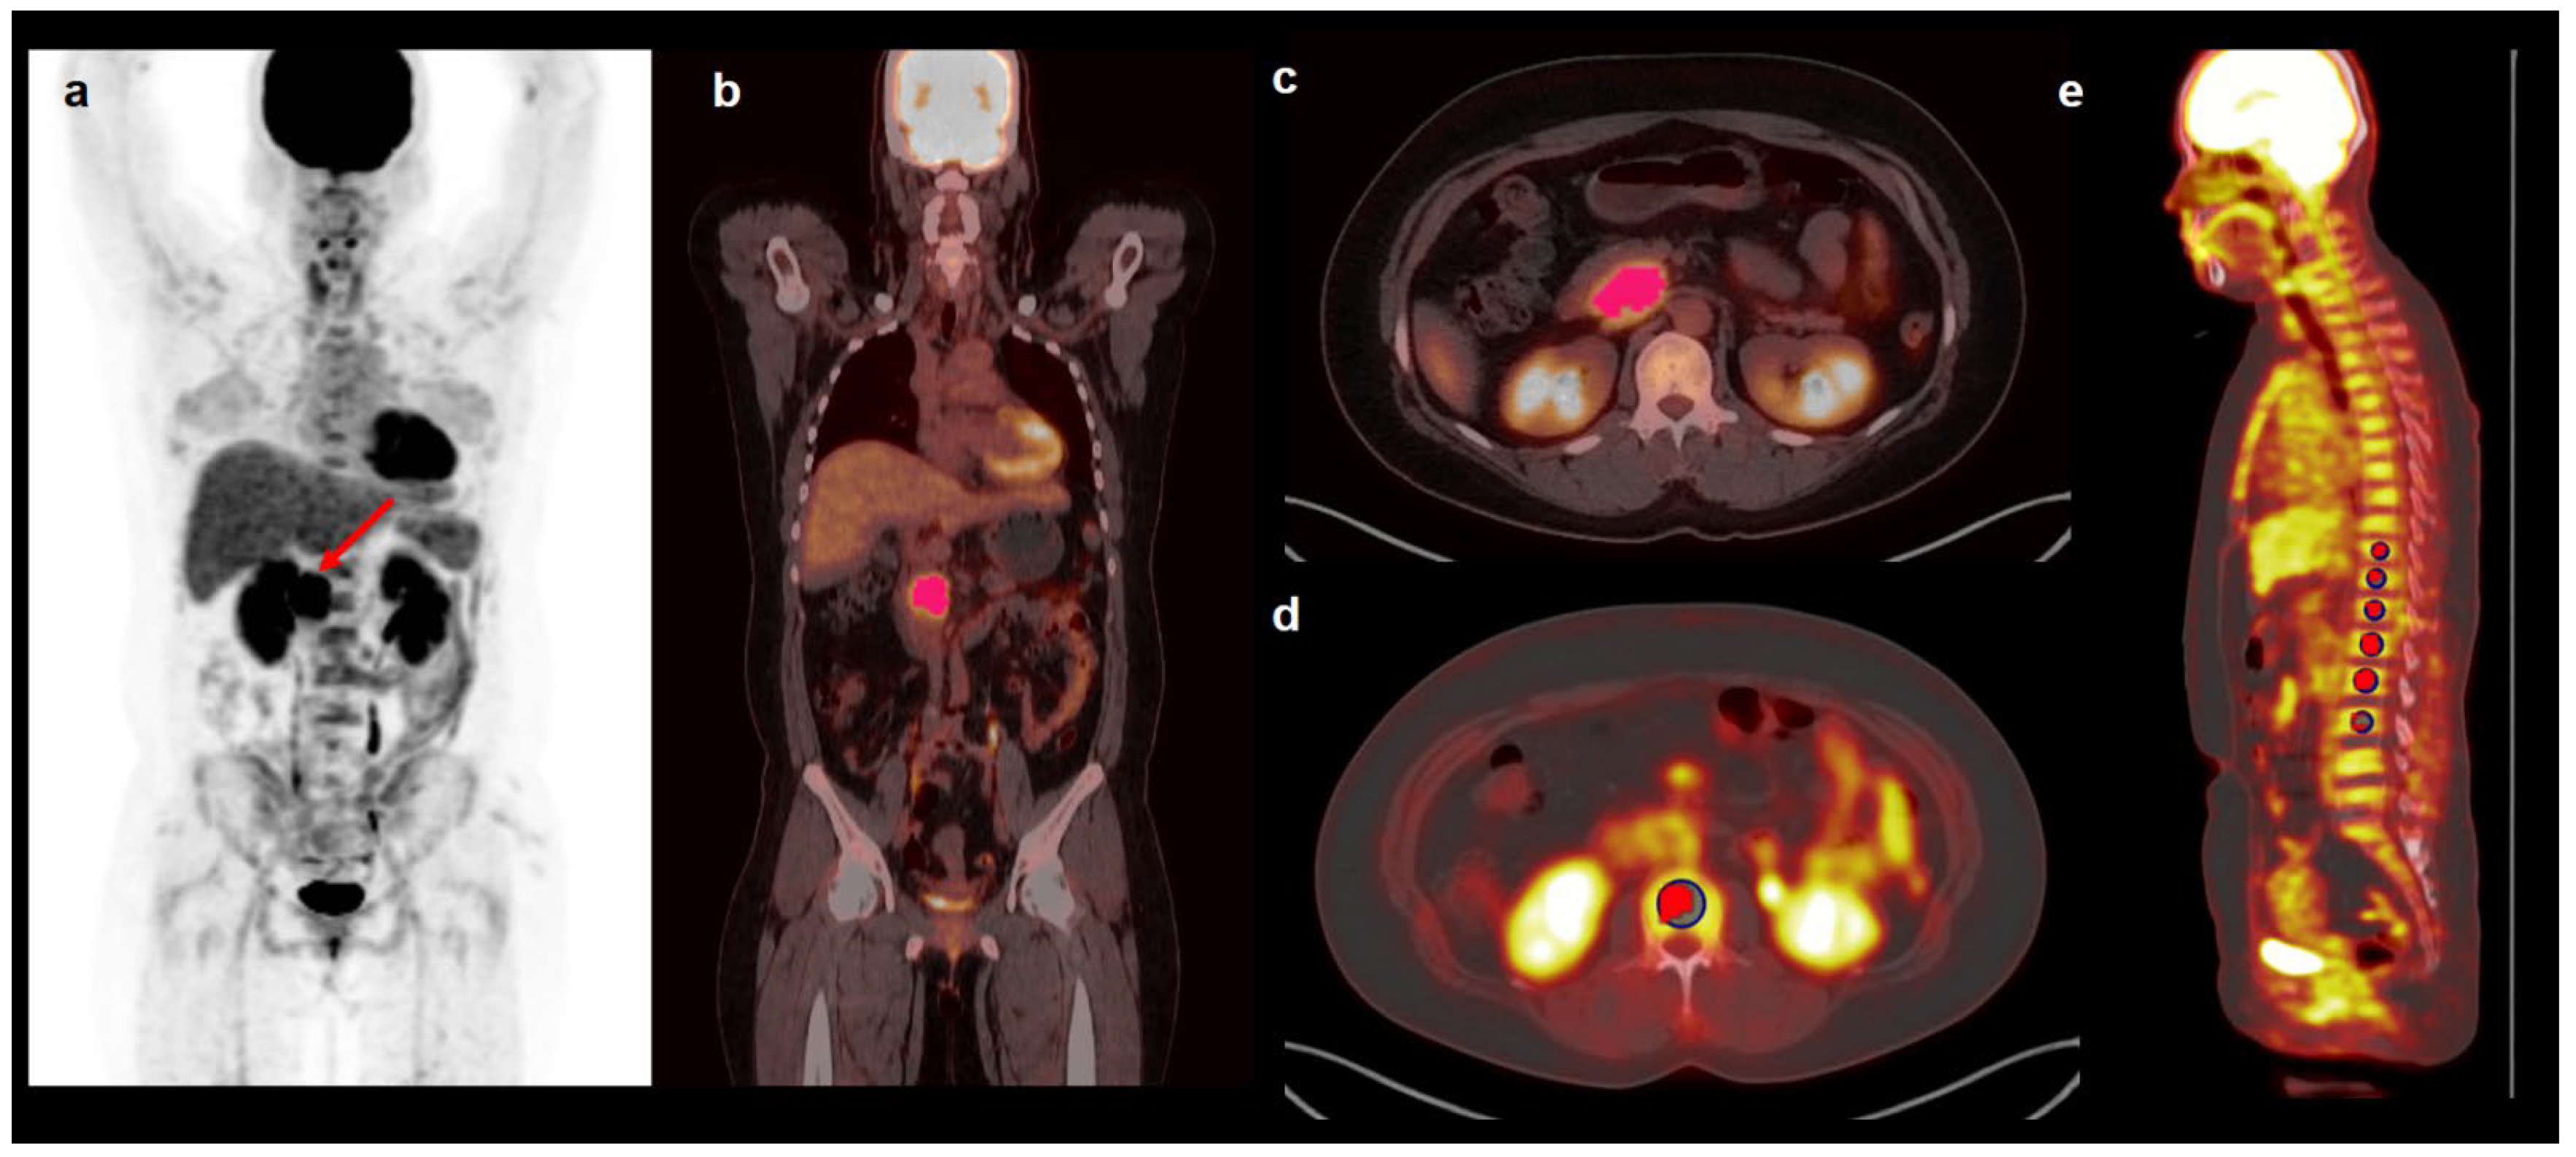

2.3. PET/CT Image Analysis